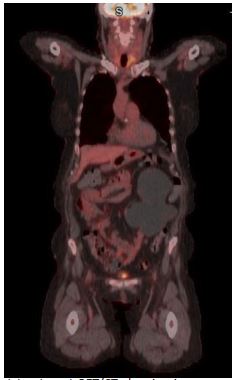

A Fluorodeoxyglucose Positron Emission Tomography/Computed Tomography (FDG PET/CT) scan revealed FDG-avid masses involving the spleen, left thyroid as well as left cervical, supraclavicular, upper mediastinal, and portacaval lymphadenopathy (Figure 3). Her bone marrow biopsy was negative for infiltration of lymphomatous cells.

Figure 3: Pretreatment PET/CT showing FDG-avid masses involving the left thyroid with left cervical, supraclavicular, upper mediastinal regions.